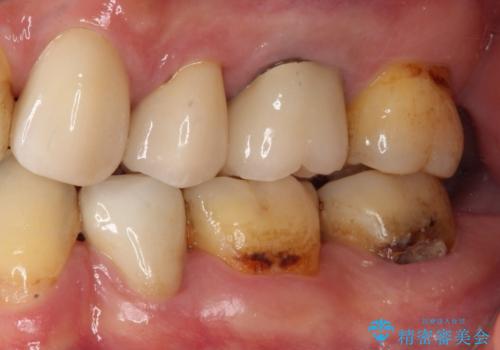

- 奥歯がしみるとのことで来院された患者様です。

診査をしたところ、目視でも明らかな、とても大きなむし歯があありました。

既に治療により詰め物が装着されている歯であったため、オールセラミッククラウンによる補綴治療を選択することとしました。